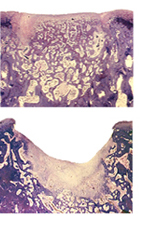

Healthy cartilage vs osteoarthritic cartilage [13]

Healthy cartilage vs osteoarthritic cartilage [5]

Articular cartilage is the cartilage found between joints that reduces friction and acts as a shock absorber; it is flexible tissue composed of chondrocytes embedded in dense extracellular matrix (ECM)[1].Because this cartilage gets so much wear, some deterioration is inevitable. However, excessive deterioration caused by sports injuries, overuse, birth abnormalities, or osteoarthritis can be debilitating. Because cartilage is an avascular area, blood cannot bring nutrients, enzymes, or proteins to injured cartilage. Over 6 million people visit the hospital for cartilage damage every year, and osteoarthritis, or arthritis due to the degradation of articular cartilage, affects 33% of U.S. adults 65 years of age or older [2]. Osteoarthritis is a disease that breaks down articular cartilage and results in pain and loss of joint function. Osteoarthritis affects approximately 27 million Americans [3]. Health care costs related to cartilage damage are staggering. The total annual cost of living with osteoarthritis is $5,700/year per patient [4]. Job-related osteoarthritis costs are estimated at $3.4-$13.2 billion/year. Additionally, hospital related costs for total knee and hip replacements are estimated at $28.5 billion/year and $13.7 billion/year respectively. These statistics are merely for osteoarthritis and knee/hip replacements; they do not take into consideration various arthroscopic surgeries for cartilage debridement, tear suturing, etc., signifying that the potential market for an effective engineered cartilage is large and undertapped. The most limiting aspect of damaged articular cartilage is the absence of vascularization, which limits the blood and bone marrow to the cartilage tissue thus limiting repair and remodeling capabilities [1]. At the moment, we can repair cartilage but not fully restore it. The repairs have varying levels of efficiency and varying lifespans. Current engineered cartilage does not have the same properties of native cartilage and is insufficient. The goal is to one day be able to completely regrow new cartilage that perfectly matches the patient's needs, in size and immunocompatibility.